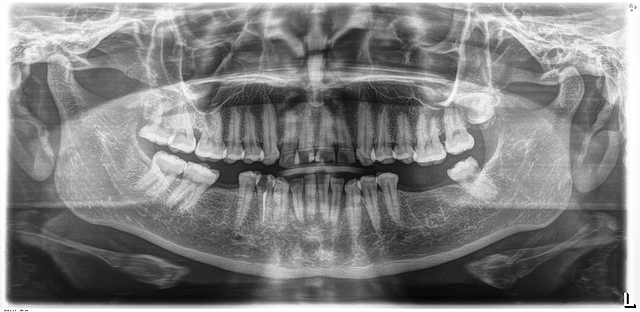

• Análisis radiográfico

Análisis radiográfico

Se mandó a tomar la radiografía panorámica donde se observó la posición del OD 1.8, 2.8, 3.8 y 4.8. La reabsorción osea horizontal, restauración filtrada del OD 1.1 y 2.1. El OD 4.4 previamente tratado.